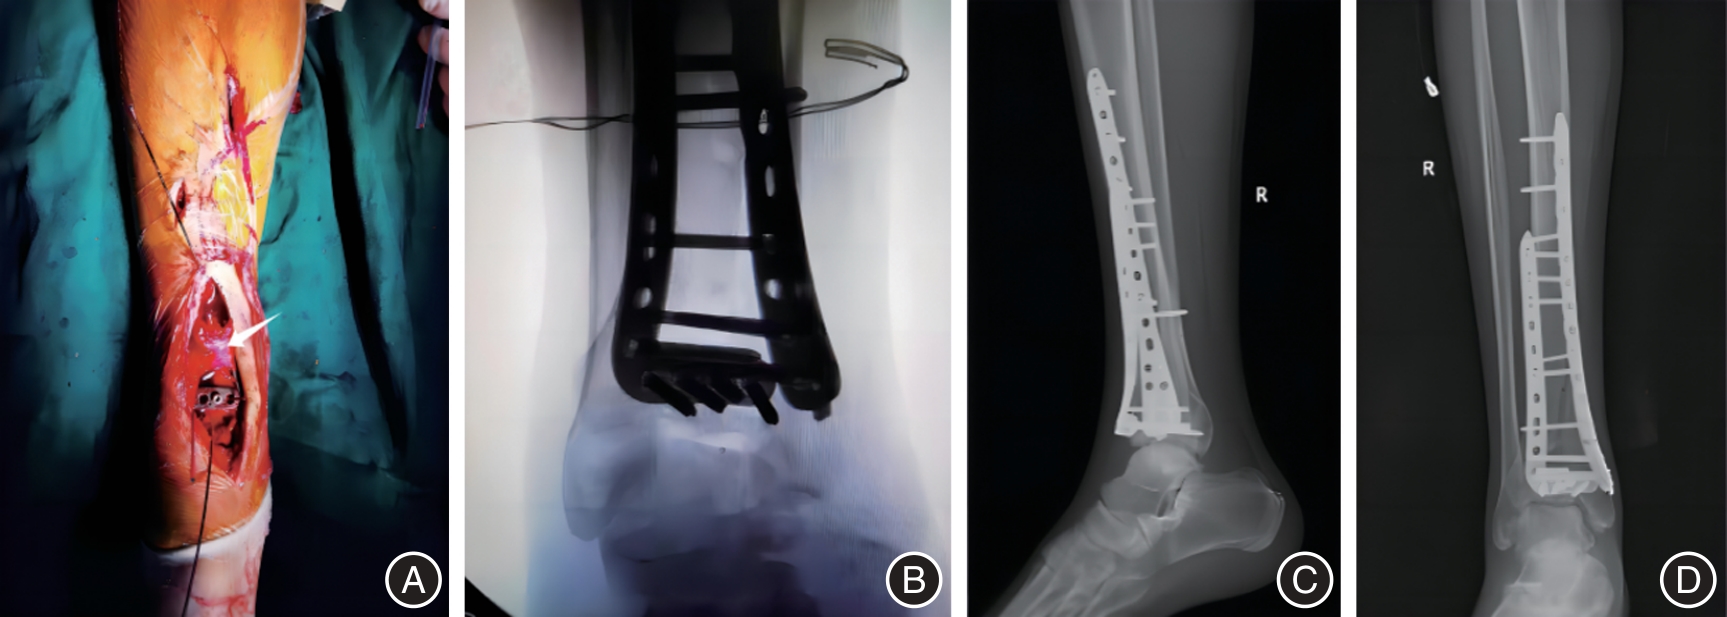

Youqiang ZHANG,Ling YAN,Wei LIAO,Guang WANG,Xiaoheng CHEN,Rui FAN,Zuwei. LIU. Study of modified anteromedial approach and preserves the superior extensor retinaculum for clinical effect of Pilon fracture[J]. The Journal of Practical Medicine, 2025, 41(3): 358-364.

21 | 胡远军, 成瑞萍, 史会明, 等. 改良前内侧入路治疗Ruedi-Allgower Ⅲ型Pilon骨折的疗效[J]. 实用骨科杂志, 2020,26(2): 124-127. |

22 | 周骅, 薛剑锋, 周朝, 等. 改良前内侧手术入路对Ruedi-Allgower Ⅲ型Pilon骨折的临床效果分析[J]. 浙江创伤外科, 2022,27(1): 139-140. |

23 | 黄绍飞,杨云平,黄海. 改良前内侧入路治疗复杂闭合性Pilon骨折的疗效[J]. 中华实验外科杂志, 2020,37(11):2121. |

24 | 付鲲鹏, 张晓敏, 赵艳霞, 等. 改良前内侧入路与前外侧入路对C3型Pilon骨折复位及疗效的影响[J]. 西南国防医药, 2020,30(8): 739-742. |